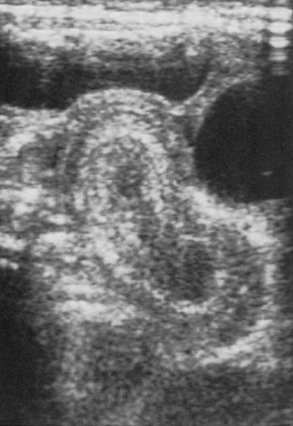

The use of abdominal ultrasound (US) for the evaluation of intussusception was first described in 1977.20 Since then, most institutions have adopted it as a screening tool because of the lack of radiation exposure, ability to identify pathologic lead points, and decreased cost.21,22 The characteristic finding on ultrasound has been referred to as a ‘target’ or ‘doughnut’ lesion (Fig. 38-4), which consists of alternating rings of low and high echogenicity representing the bowel wall and mesenteric fat within the intussusceptum in a transverse plane. The ‘pseudokidney’ sign is seen on longitudinal section (Fig. 38-5). This pattern is secondary to the edematous walls of the intussusceptum within the intussuscipiens. Ultrasonography can also guide the therapeutic reduction of an intussusception.21 Equivocal findings using this modality should mandate a conventional contrast or air enema.23